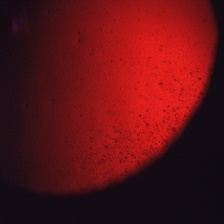

The primary pathology of MECD lies in the corneal epithelium and its basement membrane. Histopathologically, it is described by the development of clusters of small, clear intraepithelial cysts diffusely distributed at different levels within the corneal epithelium, which is irregular in thickness.[11] The transparent microcysts are roughly the same size and are mostly found in the basal epithelial cells. They contain degenerated epithelial cells and cellular debris that are periodic acid-Schiff (PAS) positive[4] and diastase- and neuraminidase- resistant.[11] Degenerated cellular debris within the intraepithelial microcysts manifests autofluorescence in ultraviolet (UV) light and it stains with the Hale colloidal iron technique for negatively charged substances such as glycosaminoglycans (GAGs). Other distinct pathological findings include the presence of electron-dense filamentary and granular material, the pathognomonic so-called peculiar substance, in the epithelial cells, and vacuolated, homogenous substance in the epithelial cysts (most commonly) and epithelial cells.[4] They may coalesce to form refractile lines and become more opaque.[17] The epithelium adjacent to the cysts remains clear.[5] Light microscopy shows the epithelial basement membrane to appear coarse, variably abnormally thickened, and multilaminar. Bowman layer and the corneal stroma are spared and remain intact.

- Retroillumination: the intraepithelial microcysts appear as refractile transparent dew drops[11] and the vesicles present isolated.[22] The characteristic bleb pattern of Meesmann corneal dystrophy can be best seen upon retroillumination.[23]